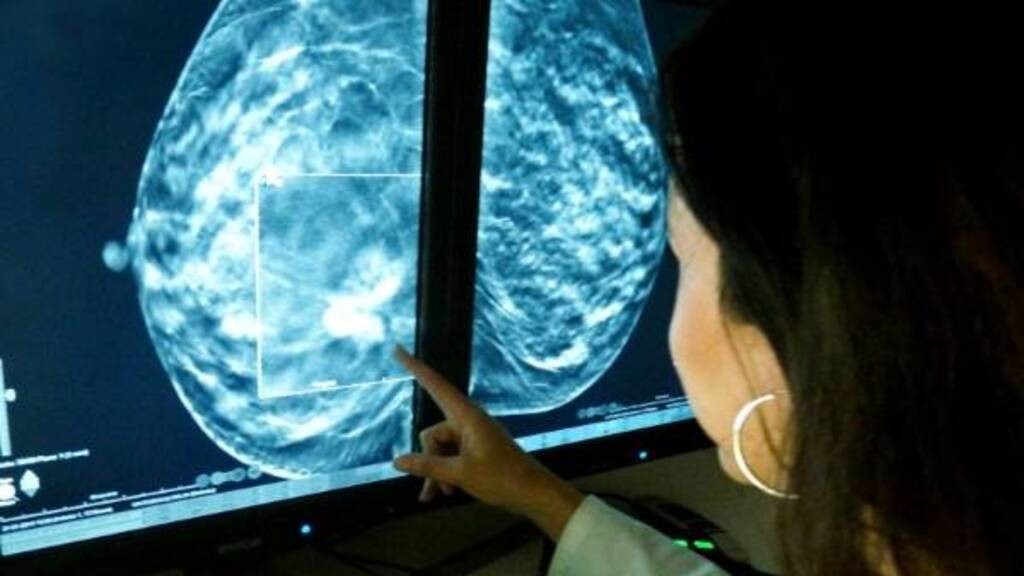

Octubre es el mes de la concientización sobre el cáncer de mama, por eso, la Provincia de Buenos Aires realizará mamografías gratuitas, sin necesidad de pedir turno previamente, en 20 hospitales públicos bonaerenses los días jueves 17, viernes 18 y sábado 19, de 8 a 20.

El tumor más frecuente a nivel mundial y la Provincia no es la excepción a esa estadística, donde se producen 2.300 muertes anuales por este tumor que constituye el tipo de cáncer más frecuente. No obstante, la buena noticia es que, con controles de salud anuales, detección temprana y tratamiento oportuno se puede prevenir, tratar y curar en la mayoría de los casos.

La funcionaria destacó que, en los últimos cuatro años, desde que se creó el Instituto Provincial del Cáncer, «se fortaleció el sistema sanitario con la incorporación de 11 nuevos mamógrafos digitales instalados en hospitales públicos, lo que representa un aumento del 25% en la capacidad instalada de este equipamiento clave para el diagnóstico oportuno». También, se sumaron 19 tomógrafos, indispensables para el tratamiento de ésta y otras enfermedades oncológicas.